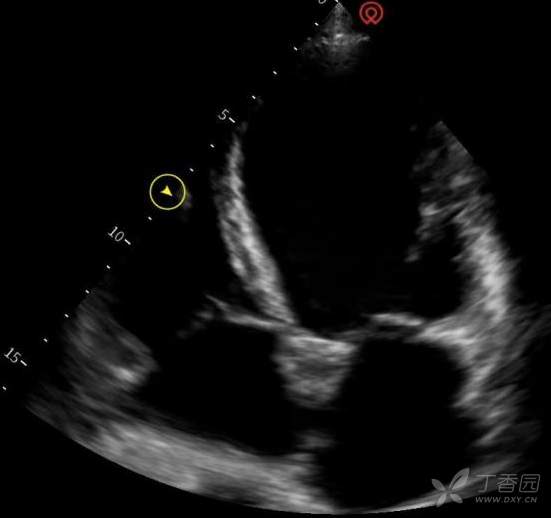

心脏超声:左房 49 mm,右房 40 mm,左室舒张末内径 68 mm,右室舒张末内径 39 mm,左室 EF 26%。全心扩大,左室室壁运动弥漫性减低。二尖瓣探及少-中量反流信号,三尖瓣及主动脉瓣探及少量反流信号。舒张期二尖瓣前向血流频谱 E 峰 < A 峰。TDI 示二尖瓣瓣环频谱 e' < a'。

肺部超声:左肺上 BLUE 点检查可见 B 线,左肺下 BLUE 点检查可见 B 线,左 PLAPS 点检查可见 B 线,右肺上 BLUE 点检查见 B 线,右肺下 BLUE 点检查见 B 线,右 PLAPS 点检查见 B 线。